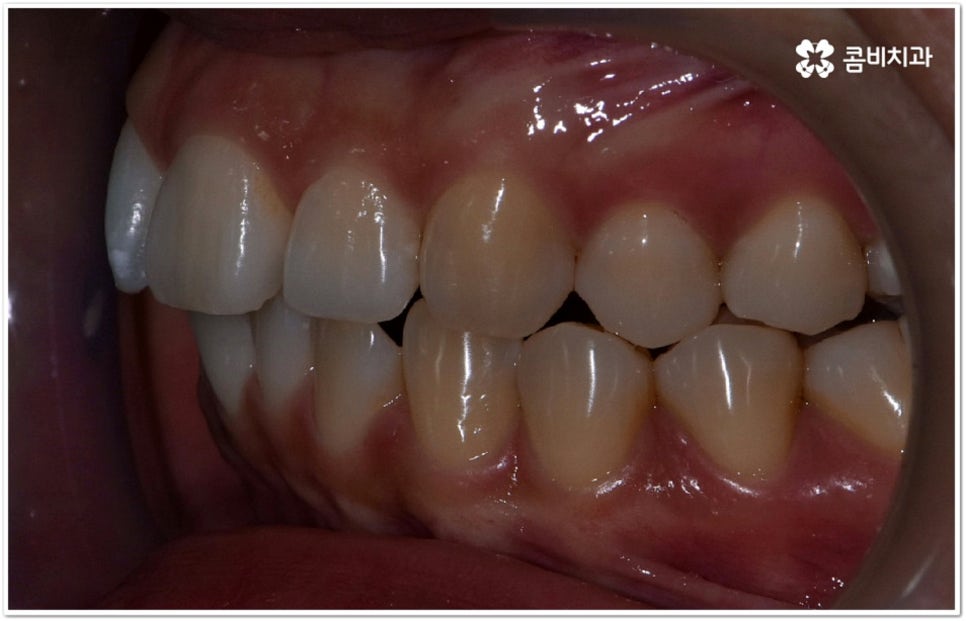

사실 치아가 많이 겹쳐서 삐뚤빼뚤하면 보기에도 좋지 않고 사이사이에 음식물 찌꺼기가 끼어서 충치 같은 구강 질환도 더 자주 발생할 수 있기 때문에 환자분들의 입장에서도 교정 치료를 고려하시는 경우가 많지만, 아주 살짝 덧니가 있을 때는 교정에 대해서 별로 심각하게 생각하지 않으실 수도 있는데요. 이런 덧니는 사람에 따라 오히려 매력 포인트가 될 수도 있기 때문에 스스로 느끼기에 문제가 아니라고 생각한다면 반드시 교정 치료를 해야 하는 것은 아니지만, 만약 입을 벌렸을때 잘 보이는 앞니, 송곳니 등이 덧니라서 웃거나 말을 할 때 신경이 쓰이거나 자기도 모르게 손으로 가리는 습관이 들 정도로 자신감이 떨어진 경우라면 한 번쯤 고려해 보셔도 좋을 거예요. 특히 위아래 맞물림에 문제가 없고 구조적인 부분과 관련된 원인이 크지 않다면 덧니부분교정 을 통해서 보다 빠르고 간편하게 개선이 가능한 케이스도 있기 때문에 꼼꼼한 검진을 통해 자신의 상황이 어떤지부터 알아보시길 권유드리고 있습니다.

덧니의 원인에는 여러 가지가 있는데 대표적으로는 유치가 너무 일찍 빠져서 영구치가 제대로 자리를 잡지 못했거나 턱뼈의 크기와 치아 크기가 조화를 이루지 못하는 경우 등 공간이 부족한 상황을 생각해 볼 수 있어요. 덧니는 주로 송곳니가 가장 흔하나, 치열이 공간이 부족할 경우 이론적으로는 어떤 치아라도 덧니가 될 수 있어요. 이때 원인과 정도를 꼼꼼하게 파악하여 만약 해당 부위만 부분 교정이 가능하다면 덧니부분교정 치료를 할 수 있는데요. 덧니부분교정 을 이용하면 원하는 부위에만 브라켓을 부착하여 치아 이동을 시키기 때문에 전체 교정에 비해서 간편하며 치료 기간도 6~8개월 정도로 줄어들고 통증도 많이 감소될 수 있습니다. 비용적인 부담도 덜하며 (삐뚤어진 정도나 상태에 따라 다르겠지만) 보통 덧니부분교정 의 경우 비발치 과정으로 진행되기 때문에 환자분들의 입장에서는 덧니부분교정 을 많이 선호하시는 편이라고 할 수 있어요. 상황에 따라 미니스크류, 치간삭제, 악궁확장장치 등 환자에게 맞는 비발치 방법을 이용하여 도움 받을 수 있습니다.

하지만 모두에게 덧니부분교정 을 적용할 수 있는 것은 아니므로 먼저 3D CT와 같은 정밀 검사 장비를 통해서 턱의 구조적 특성 및 치열과 교합 등 구강 내부 상황에 대해 세세하게 검진을 하고 충분한 상담을 통해 각자에게 적합한 계획을 세운 다음 무리하지 않게 치료를 진행할 필요가 있어요. 만약 부분 교정을 진행할 수 없다고 해도 교정 장치를 이용하여 기간이나 통증 부분의 부담을 덜 수 있으니 너무 실망하실 필요는 없을 거예요.